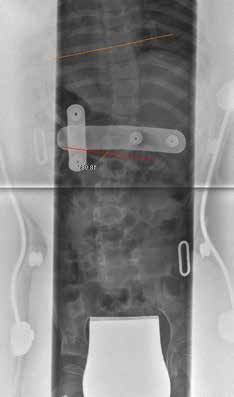

Die Patientin der Abbildung 11 leidet an einer spinalen Muskelatrophie (SMA) mit kollabierender Skoliose. Eine Spondylodese wird derzeit von den Eltern abgelehnt, so dass die Korsettversorgung die Sitzstabilität verbessern und aufrechterhalten sowie die Progredienz bremsen soll. In diesem Fall wurden Beckenring und thorakaler Ring des Korsetts getrennt und mit elastischen Stäben (Pohlidyn) verbunden. Ohne die Anbringung der dynamischen Verbindung war das Mädchen nicht mehr in der Lage, aktiv ihren Rollstuhl anzutreiben, während dies nach Montage der Stäbe wieder möglich war (Abb. 12 u. 13).